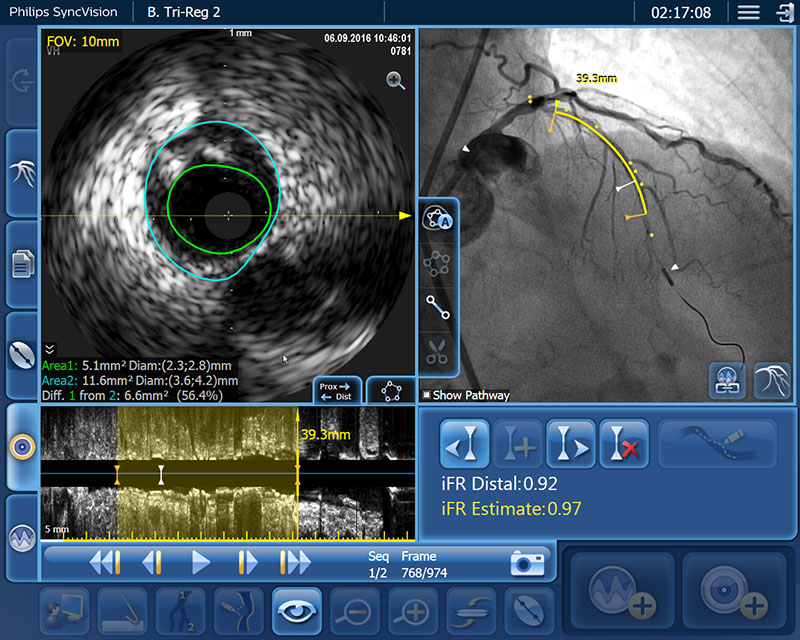

血管造影だけでは、病変の位置を特定するには不十分です。当社製品は、iFR¹,²,³の値を血管造影図にコレジストレーションすることで、高度なPhysiology評価が可能になり、血管のどの位置で虚血を起こしているのか正確に見たうえで、治療戦略を決定することができます。

iFR コレジストレーションでは血管拡張剤が不要で、時間のかかるプルバック装置の操作もなく、憶測ベースでの評価をなくします。

iFR コレジストレーションは手動プルバックにより、ワイヤーを引いた距離の自動校正が行われます。そのため、血管造影図および、圧のトレンドライン上の血管長も把握できます。

「クリック&ドラッグ」の長さ計測により、治療戦略の策定を支援

IVUS および iFR 情報を血管造影図と組み合わせた長さ計測は、ステントがPCIの成功を満たすものであるかどうかの判断を支援します。